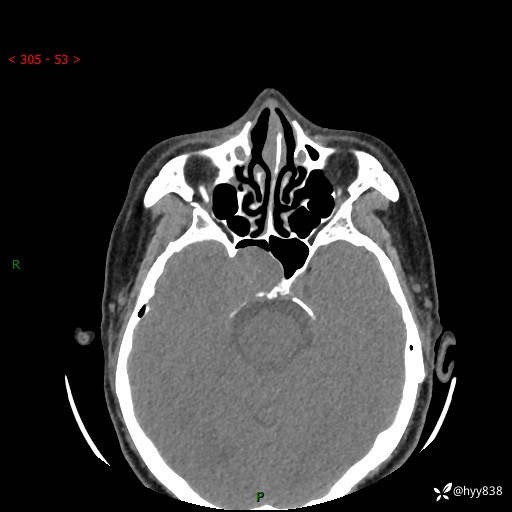

蝶鞍CT平扫